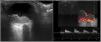

Se presenta el caso de un varón de 23 años, procedente de Mali, que acudió a urgencias por dolor ocular y pérdida de visión del ojo derecho. Al examen físico se apreció hiperemia conjuntival, pupila arreactiva, Tyndall positivo, sinequias posteriores y rubeosis del iris derecho. Con el fondo de ojo se visualizó una lesión coroidea derecha con desprendimiento de retina asociado, que fue confirmada por una ecografía ocular (fig. 1). También, se apreció una adenopatía submandibular derecha de consistencia dura y dolorosa.